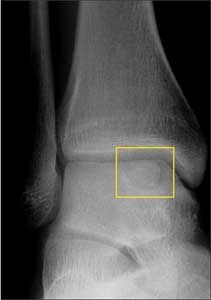

An increase in talus fractures among snowboarders might be related to the use of a soft boot that does not adequately protect the ankle during crashes. Fractures of the talar dome primarily occur on the posterolateral or anteromedial aspect. Often the fracture is not visible on radiographs. It is important to distinguish a talar dome fracture from other ankle problems.